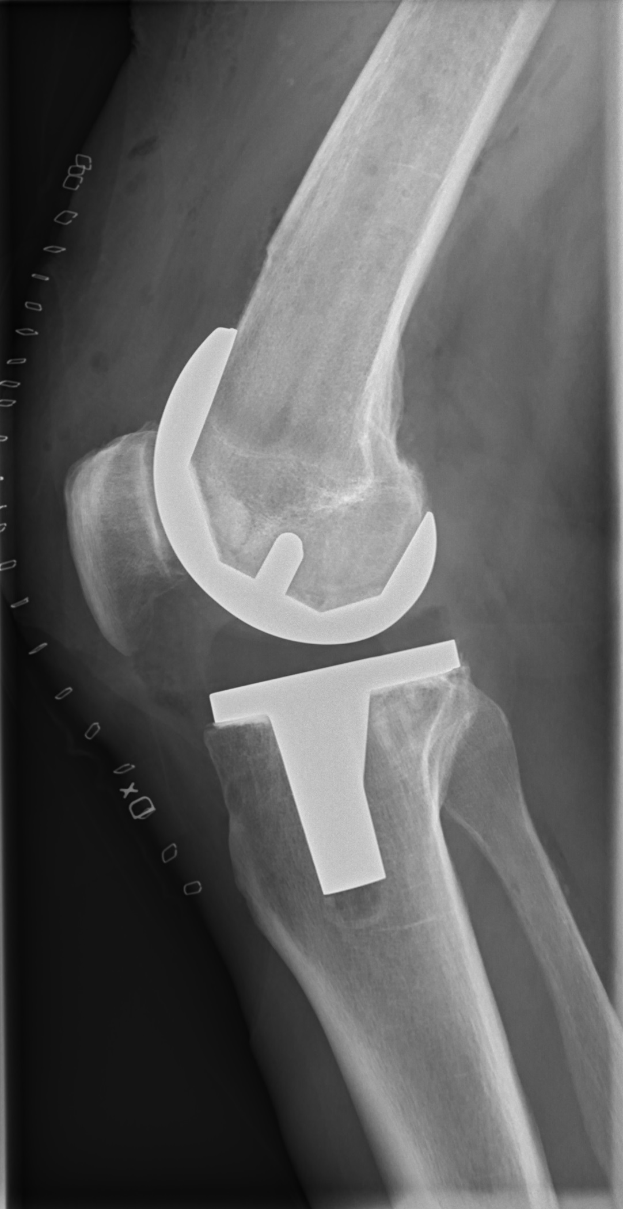

Ein Röntgenbild eines menschlichen Beins mit einer sichtbaren Fraktur im Kniebereich, möglicherweise eine Bänderverletzung.Angelina Reinhardt